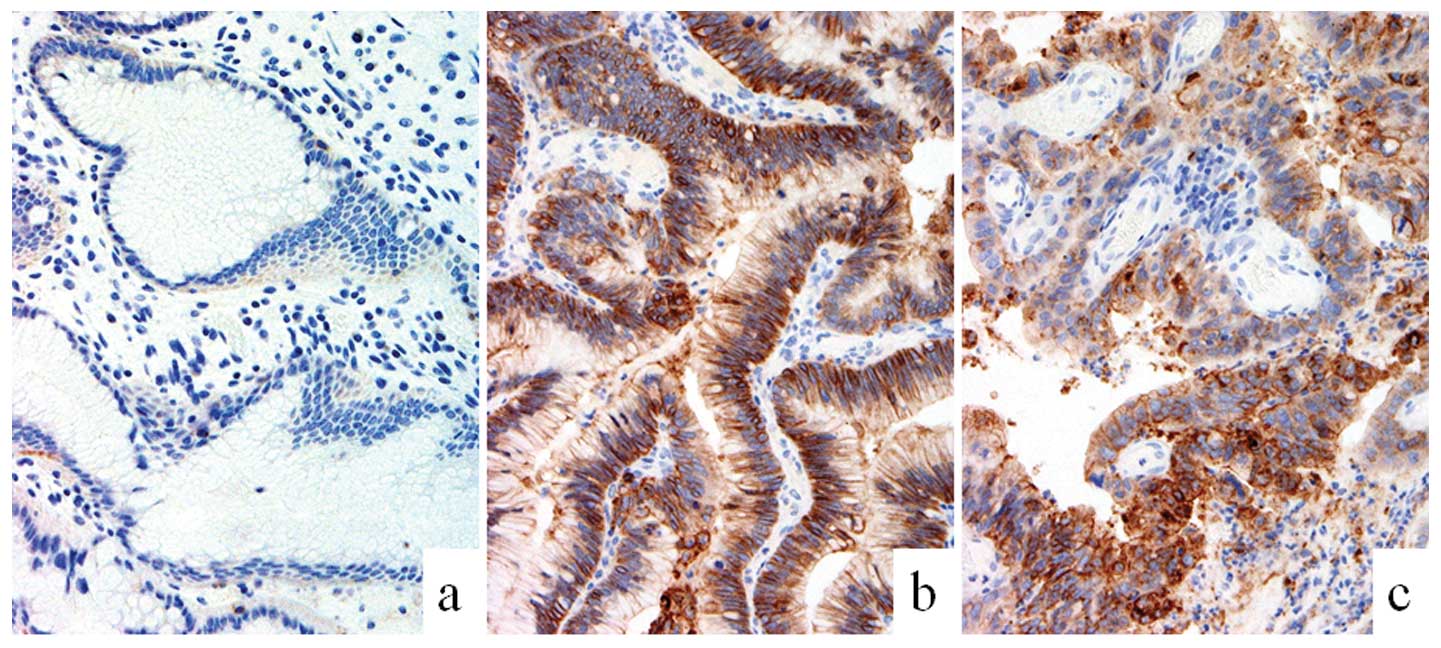

The present immunohistochemical study found that

MUC5AC was immunopositive in the hyperplastic, dysplastic and

carcinoma regions of the polyps; while this marker was detected in

the hyperplastic and dysplastic areas only, but not in the

carcinomatous component, in one case. These observations suggested

that the lesions were mostly of the gastric mucin type (Fig. 3). Furthermore, MUC2 expression was